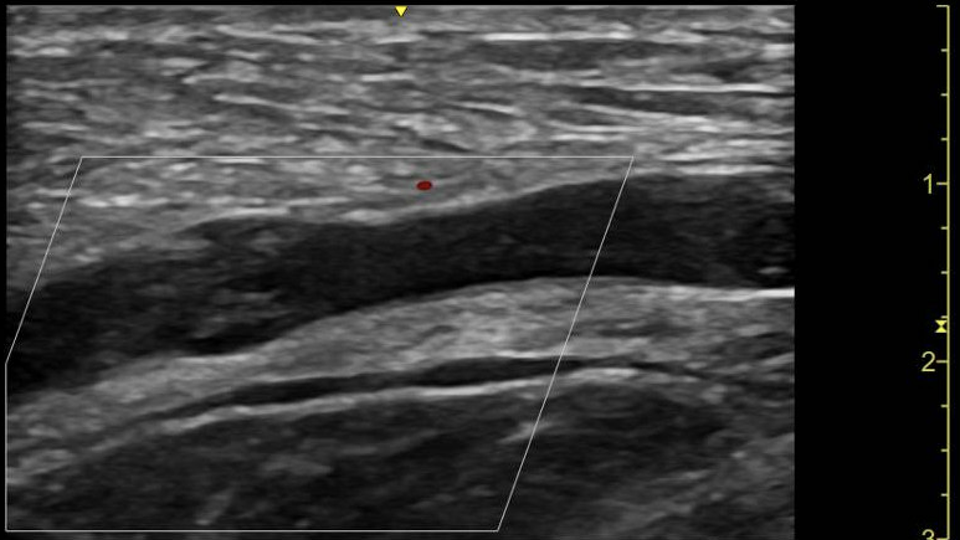

Bedside fundoscopy remains an important component of these assessments 7. Despite this, clinical utilisation by non-specialists has been declining. Contributory factors to this include lack of equipment or knowledge to perform the examination, perceived disapproval from seniors and low perceived clinical utility 6.Bedside ocular ultrasound (BOUS) has been shown to be a useful non-invasive clinical adjunct to assess for the presence of optic disc swelling, demonstrating sensitivities between 90-100% and may offer an alternative approach to this part of the assessment 10.